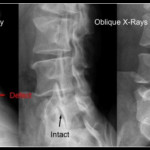

■ 腰椎分離症(腰の痛み)

腰椎分離症は、腰椎の疲労骨折。

特に反る動作や回旋動作の多い競技で発症します。

ここでも重要なのは、

股関節伸展制限

胸椎の可動性低下

体幹インナーマッスル機能低下

によって腰椎に代償的ストレスが集中している構造です。